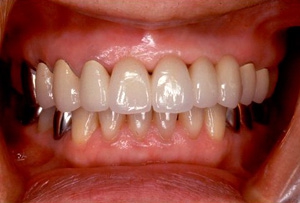

術後口腔内(正面観)もう入れ歯は要らなくなりました。

義歯装着後 バネが無いので入れ歯を使っているのが、外からはわからないくらいです。

義歯装着時正面像

口腔内装着

術後

術後 歯の尖端の透明感までよく再現できている。